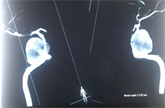

The non-symmetrical presentation of the cavernous sinus on the CT-Scan was more revealing a possible carotid-cavernous lesion with a round hyperdense lesion on the right carotid-cavernous sinus helping to conclude of either aneurysmal rupture or a vascular malformation bleed (Figure 2(a)). The cerebral MRI revealed a unilateral right carotid-cavernous fistula secondary to the aneurysmal rupture (Figure 2(b)). The patient was then transferred to the neurological surgery department for further investigations and treatment. Urgent cerebral arteriography was done the same day by interventional neuroradiologists, showing right high-flow CCF, Barrow Type A from a ruptured right internal carotid artery aneurysm, venous hypertension of CS, and ipsilateral ectasia of the superior ophthalmic vein (Figure 3(a)). The arterial blood pressure, ECG, pulmonary X-Ray, Complete blood count, and blood coagulation factors were without abnormal findings.

![]()

Figure 2. (a) Contrast enhanced brain computer tomography, axial section on parenchymal window, showing a round hyperdense lesion on the right carotid-cavernous sinus (black arrow). Extraocular muscle thickening and periorbital oedema. (b) Brain MRI, axial T2-weighted sequence with spontaneous high flow unilateral right carotid-cavernous fistula secondary to the aneurysmal rupture; ectasia of right ophthalmic vein (green arrow).

Figure 3. (a) Right carotid-cavernous fistulas secondary to aneurysmal rupture. (b) Endovascular treatment with positioning detachable balloons and coils into the right cavernous sinus. (c) Immediate post-op control.